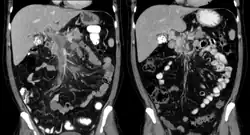

| Portal vein thrombosis seen with computed tomography. | |